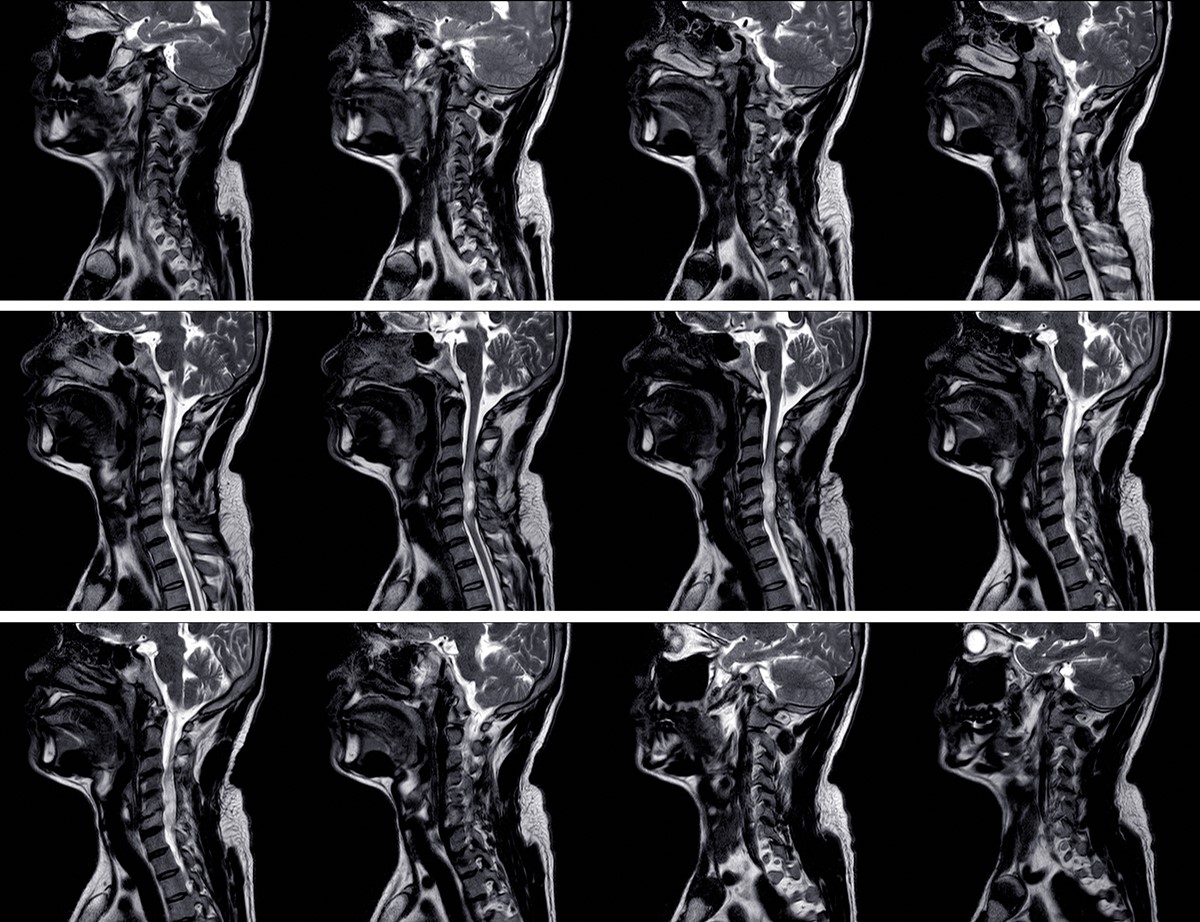

Most branchial cleft cysts are reported as slowly enlarging neck masses that are smooth. They tend to enlarge after the affected individual has contracted an upper respiratory tract infection.